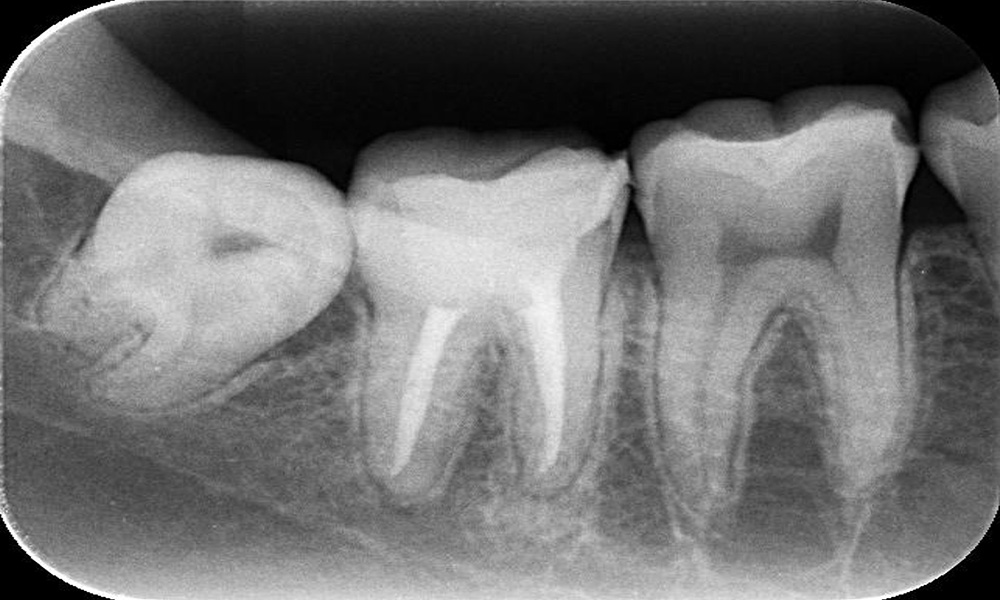

| 主訴 | 親知らずを抜きたい (親知らず、過剰歯 抜歯) |

| 治療期間 | 約1ヵ月 |

| 治療費 | 1歯 2,000~5,000円 |

| 治療内容 | 左右別日に分けて抜歯を行い縫合し翌日以降に消毒、抜糸を行った。 |

| 治療のリスク | 術後の疼痛、腫脹、痺れ |